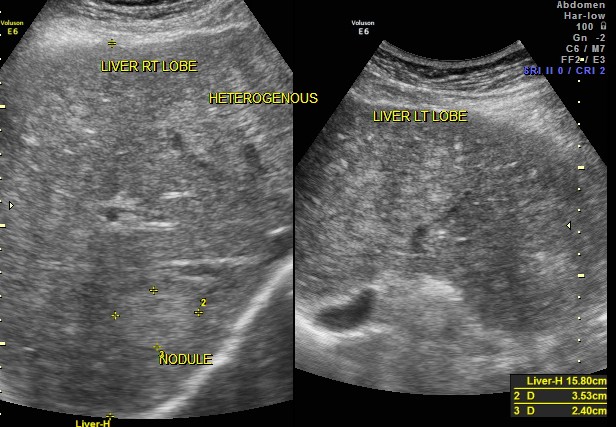

This 74 year old gentleman has been coming to me for more than 10 years for mild systemic hypertension and hypothyroidism.He used to smoke cigars until a few years ago. 3 years ago he developed unexplained giddiness and on evaluation was found to have pituitary macroadenoma. Endocrine and neuro surgical consulatations were sought and he was on cabergoline and was doing very well. In April 2012 , he came for a routine review and was asked to continue his existing medications . One week later he came again with severe right upper quadrant pain and aversion to food. There was no history of cough in the recent past. He was advised an ultrasound scan of the abdomen and the findings are as below.

CT scan of the abdomen confirmed the findings ; For further clarification PET whole body scan was done at a centre in Chennai. The following images are from that.

Extensive FDG avid hepatic metastases involving both lobes.

The biopsy report of the liver secondary was a poorly differentiated carcinoma.